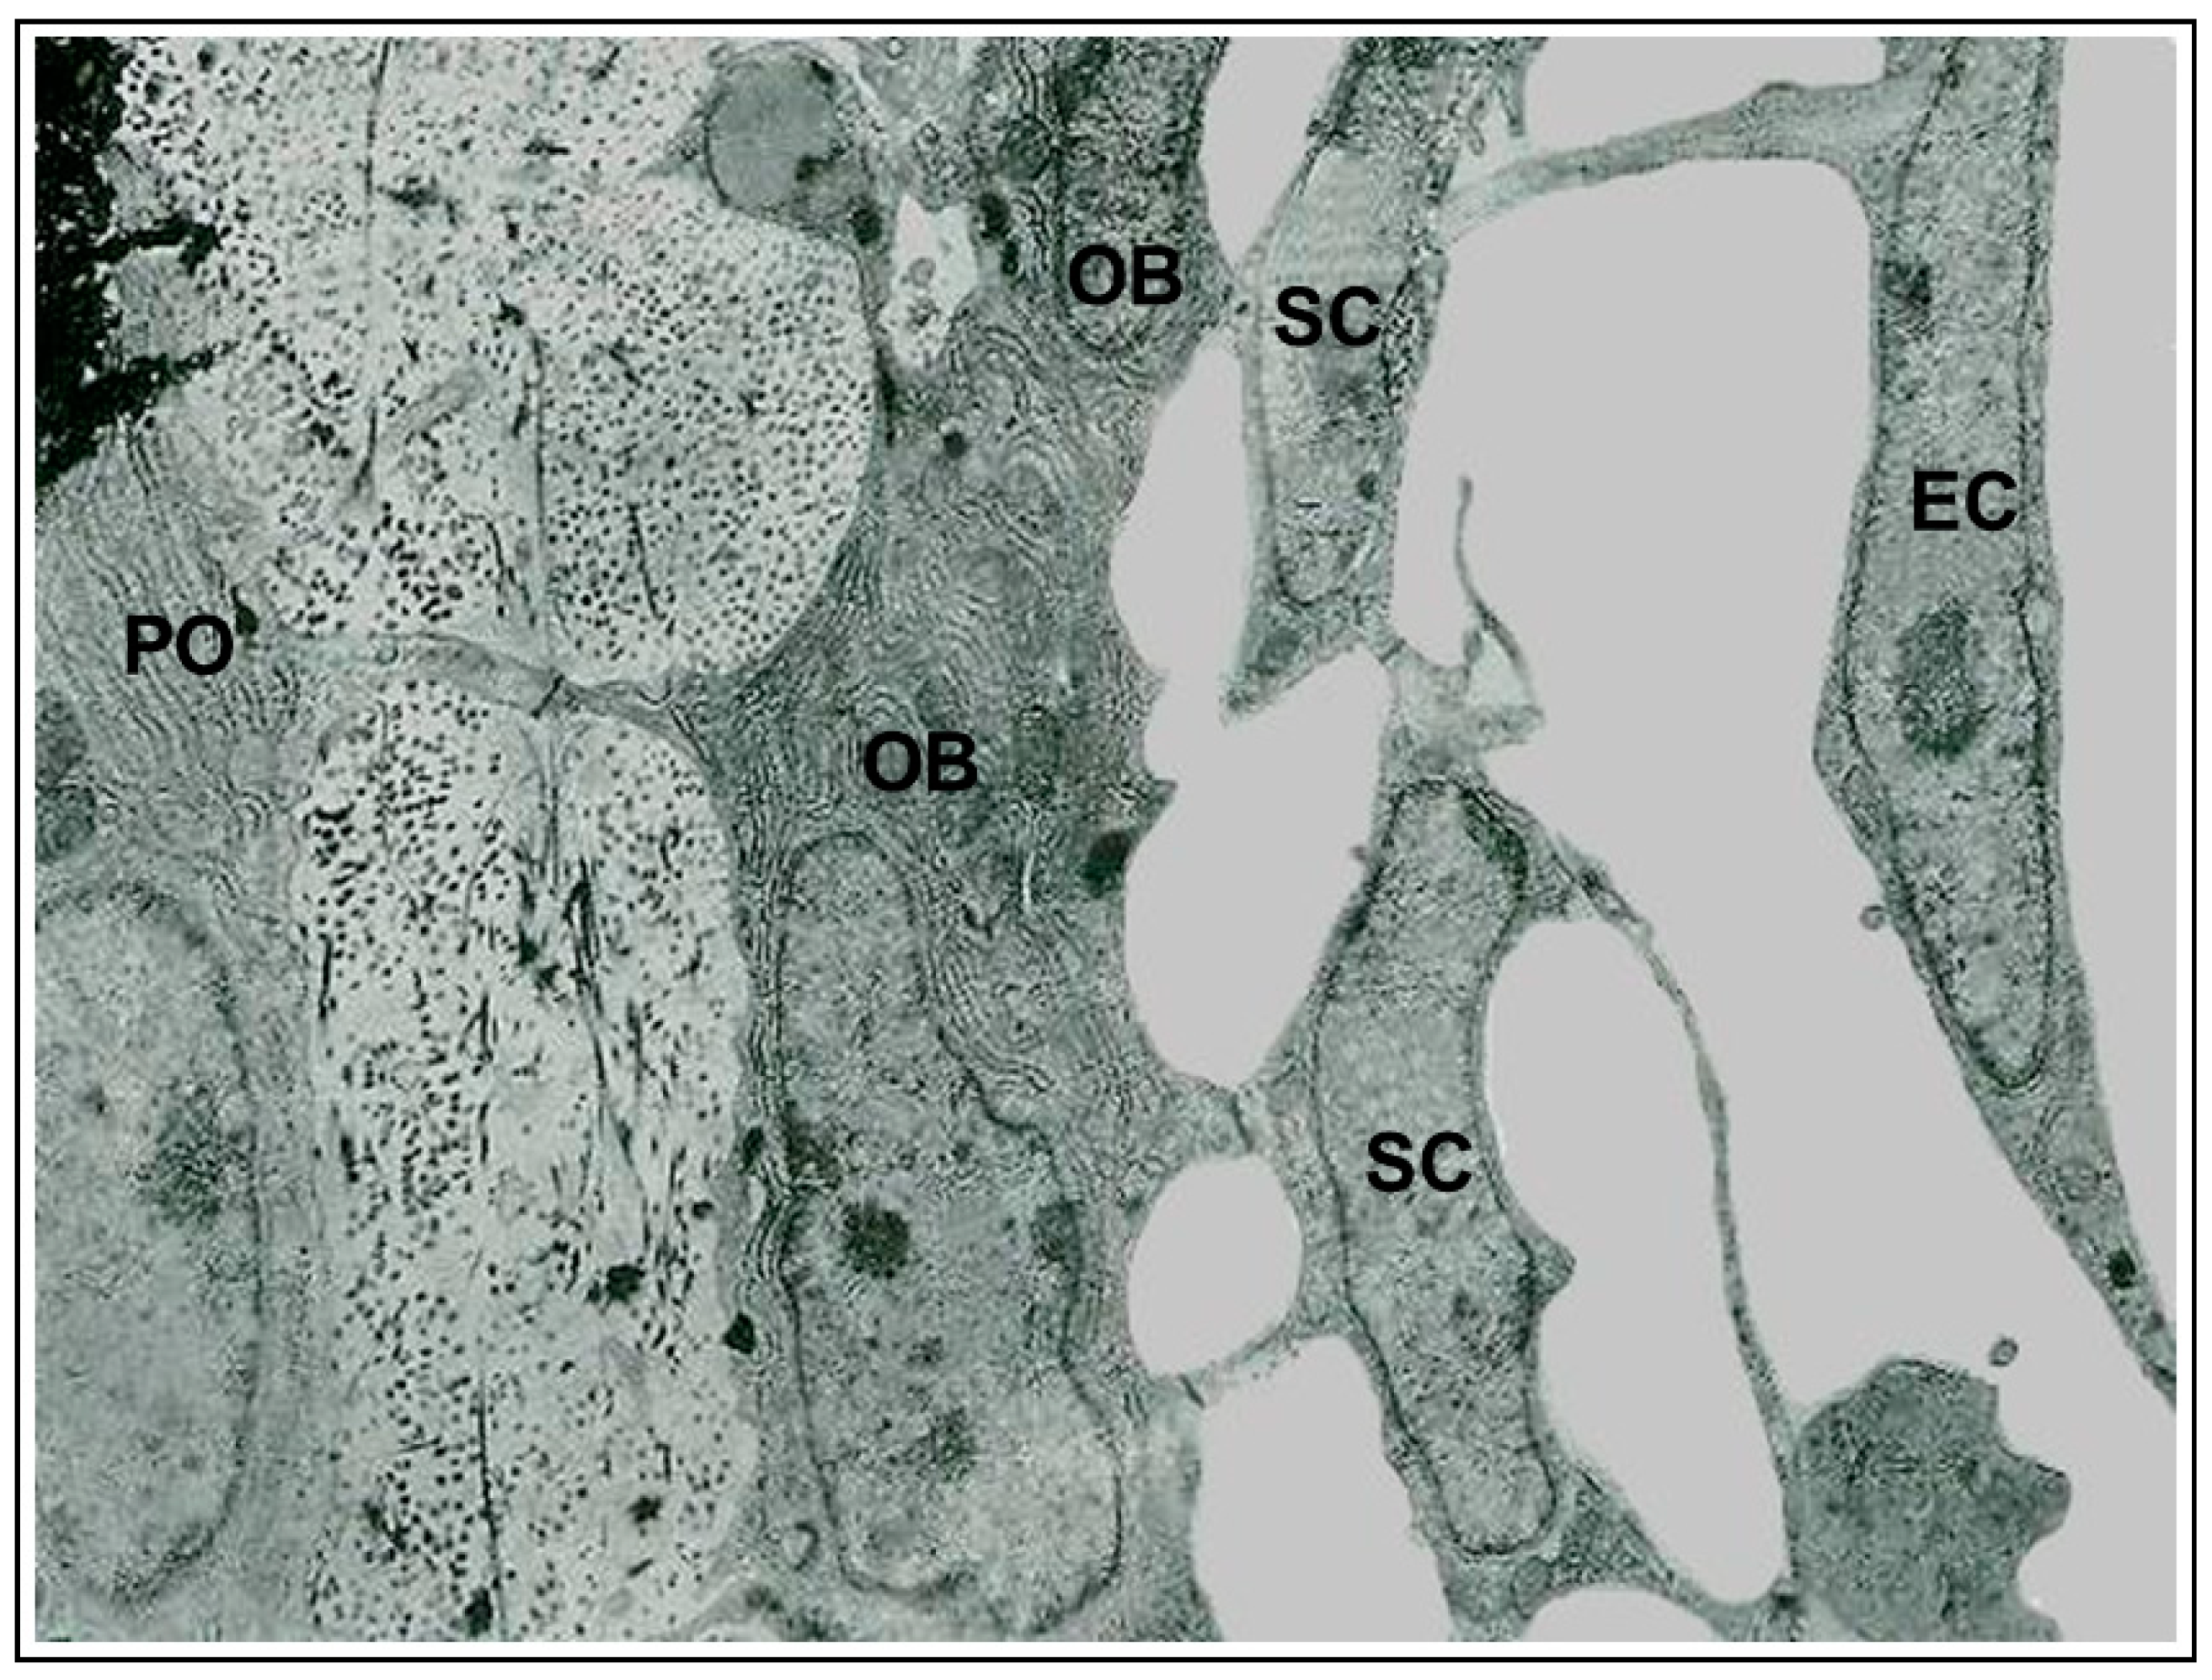

It has been known for more than a century [1][2][3] that the osteocyte originates from the osteoblast. However, the process of osteoblast-to-osteocyte differentiation has been widely investigated only at a later time point with regard to both morphological and functional aspects. The structural differences between osteoblasts and osteocytes were shown by various authors in the 1960s to1980s [4][5][6][7][8], but only afterwards was established the temporal sequence of the events that allows the transformation of the prismatic osteoblast (generally arranged in laminae facing the vascular bone surfaces) into the dendritic mature osteocyte (embedded in the mineralized matrix) [9][10][11]. Concerning the dynamic modification of the cell body of preosteocyte (i.e., the differentiating osteocyte), the amount of the cytoplasmic organelles decreases, whereas the nucleus-to-cytoplasm ratio increases depending on the diminution of its secretive activity [9]. In parallel to both the cellular body reduction in size and the modification in ultrastructure, the formation of the cytoplasmic processes proceeds with an asynchronous and asymmetric pattern, considering that the cells in differentiation are progressively further away from the vascular surface due to the osteoid secreted by the osteoblastic lamina (Figure 1): firstly, the differentiating osteocytes maintain contacts with the mature osteocytes that recruited them from the osteoblastic lamina, forming short “mineral” processes; later, they establish contacts with the migrating osteoblastic lamina, elongating slender and long “vascular” processes, issued before the complete mineralization of the surrounding osteoid. The asynchronous and asymmetrical dendrogenesis is the expression of the fact that osteocytes (as all bone cells) live in an asymmetrical environment, between the mature mineralized matrix and the vascular surface (covered by osteoblastic laminae or bone lining cells); thus, it is logical to expect that not only the osteocytes, but also the preosteocytes and the osteoblasts, are morpho-functionally asymmetric cells.

At the end of the process, the osteocytes are confined to lacuno-canalicular cavities, “prisoners” inside the mineralized matrix. Despite this fact, they are connected, thanks to the dendrogenesis process, to each other and with the bone cells on the vascular surfaces through a network of dendrities, running within the canalicular network; this condition allows osteocytes to act as “orchestrators” of bone processes [12][13]. Prerequisite for that is the existence of junctional complexes occurring among osteocyte cytoplasmic processes [7][14][15], suggesting that the bone cells of the osteogenic lineage, arranged in network (Figure 2), might act as a functional syncytium, that includes also the cells covering the vascular bone surfaces, bone lining cells [15] or osteoblasts [16].